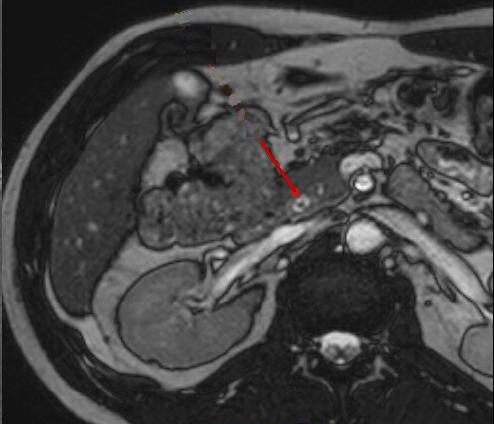

La IRM peut en detecte

si bien sur les calculs du canal choledoque avec

aspect radiologique IRM est un image arrondie

ou ovalaire a hyposignal ( fleche rouge ) . Image

radiologique IRM en coupe axiale ponderee sur T2 |